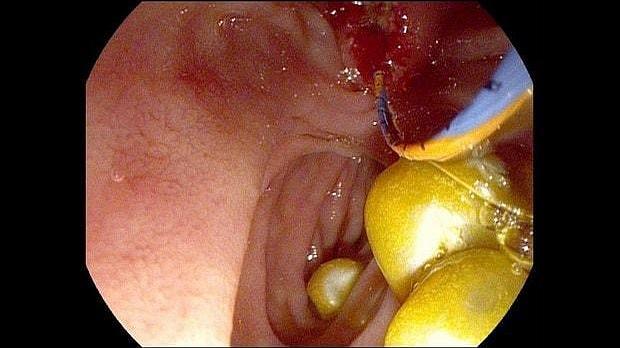

Здравствуйте. Пациентка, 32 года. Поступила на хирургическое отделение с диагнозом ЖКБ: холедохолитиаз. По данным МРТ: ЖКБ, множественные мелкие конкременты холедоха. При дуоденоскопии выявлено наличие вклиненного конкремента большого дуоденального сосочка. Выполнена прекатсфинктеротомия, получено 3 конкремента, диаметром около 0.4-0.5 см. Далее канюляция холедоха проволочным папиллотомом, выявлены многочисленные конкременты холедоха. Выполнена литоэкстракция ревизионным баллоном (на последнем фото окклюзионная холангиография - в просвете холедоха не конкременты, а пузырьки воздуха)).